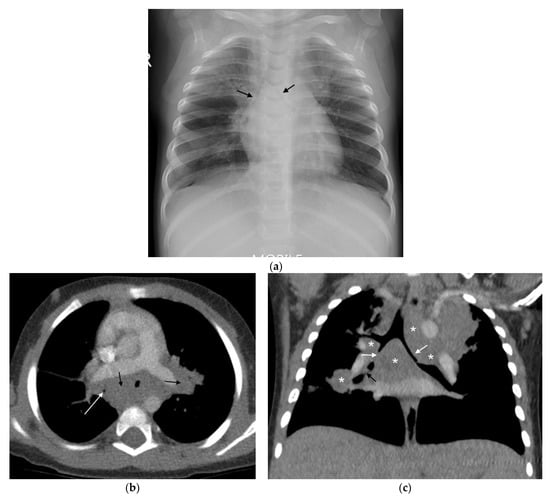

Figure 1. (a,b): Right Paratracheal and Hilar lymphadenopathy before and after treatment. (a) AP chest radiograph of a child at presentation, who later was later confirmed to have pulmonary TB, demonstrates a right-sided lobulated cardio-mediastinal margin with filling of the right hilar point (white arrows) and consistent with right paratracheal and hilar lymphadenopathy. The trachea is displaced to the left, slightly bowed and shows decreased calibre just superior to the carina. There is an oval density seen separately from the scapula in the right lung apex, which in conjunction with the lymphadenopathy, constitutes the Ghon Complex. (b) Post-treatment AP chest radiograph demonstrates complete resolution of the parenchymal focus and lymphadenopathy with a normal right cardio-mediastinal border and return of the trachea to its normal shape and position.

Right hilar adenopathy (a lobulated hilar opacity on chest radiograph) obscuring the hilar point, Figure 1, is more commonly observed than left, with left hilar nodes only evident when extending beyond the left cardiac border [27]. Paratracheal adenopathy may be difficult to distinguish from other mediastinal tissues, such as the thymus, but will extend beyond the normal mediastinal contours, and may result in airway compression and deviation [27]. Left paratracheal lymphadenopathy is rarely observed in isolation, most commonly co-existing alongside other regions of mediastinal lymphadenopathy [27]. Sub- or retro-carinal lymphadenopathy is typically seen on the lateral projection as lobulated densities inferior and posterior to the bronchus intermedius, which, in combination with the more superior aortic arch and pulmonary arteries result in the well described “doughnut sign” (Figure 2).

CT can identify lymphadenopathy in a significant proportion of children with PTB and normal chest radiographs [13]. On post-contrast CT, TB lymphadenopathy typically appears as having low attenuation centrally with peripheral rim enhancement [2] (Figure 3). The central region of low attenuation represents caseous necrotic tissue seen in tuberculous lymphadenopathy, enabling this to be distinguished from non-TB adenopathy. Alternatively, TB nodes may form a matted conglomerate with ‘ghost-like’ rim enhancement [16]. Moderately enlarged lymph nodes may occur in bacterial pneumonia, but rarely having areas of necrosis or calcification [15].